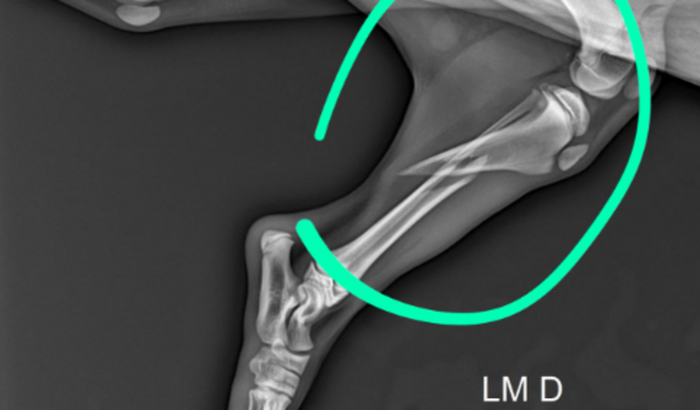

No dia 28/06/2022, ela sofreu um acidente doméstico, na qual, teve uma fratura completa na tíbia direita.

Tenho como provar tudo, exames. Raio - x